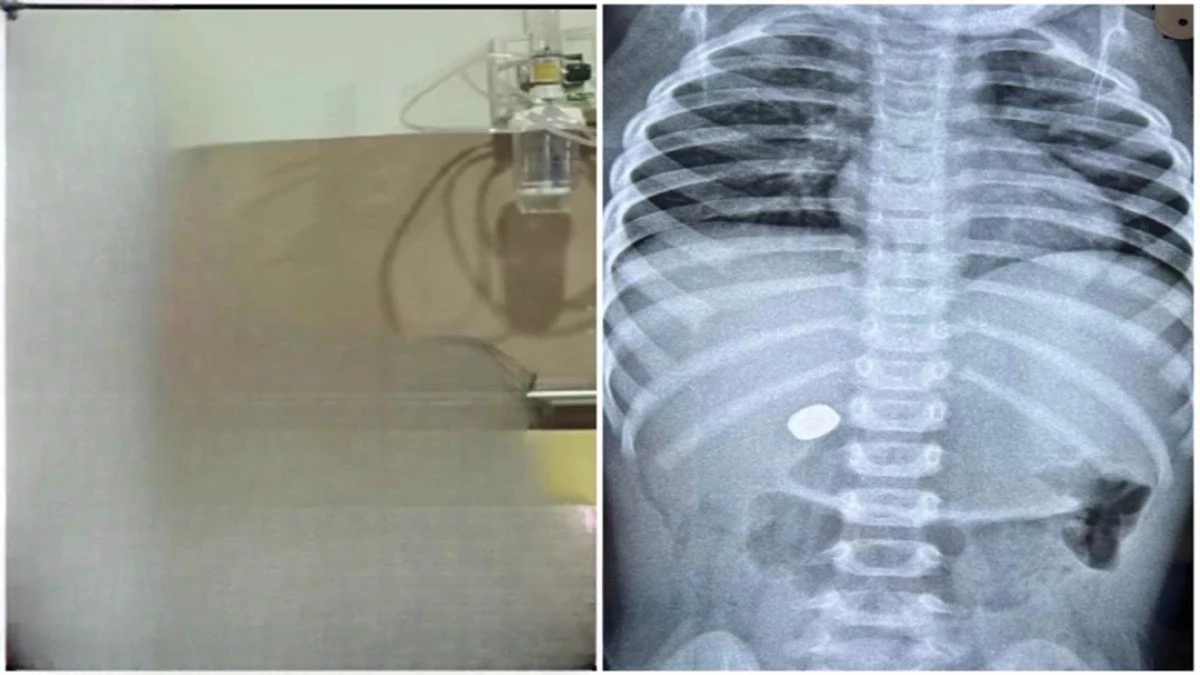

बच्चे की स्थिति देखते ही तुरंत एक्स-रे जांच कराई

हालत बिगड़ने पर बच्चा बेहोश हो गया। स्वजन उसे जिला अस्पताल सह शासकीय चिकित्सा महाविद्यालय खंडवा लेकर पहुंचे। अस्पताल के नाक-कान-गला (ईएनटी) विभाग में डॉक्टरों ने बच्चे की स्थिति देखते ही तुरंत एक्स-रे जांच कराई। जांच में स्पष्ट हुआ कि घड़ी का सेल आहार नली के निचले भाग में फंसा है और स्थिति गंभीर हो सकती है।